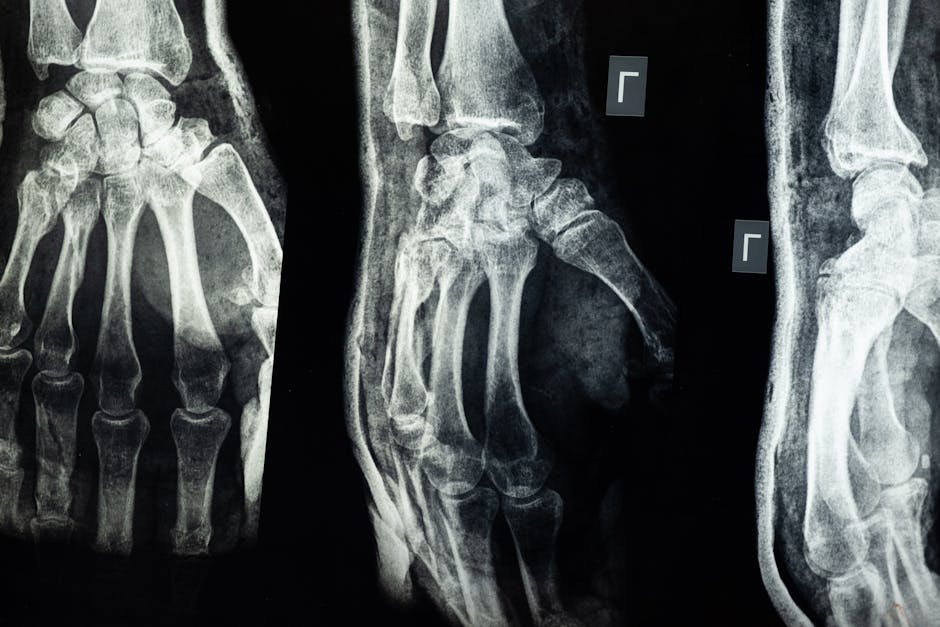

Hệ xương người là một cấu trúc phức tạp, bao gồm khoảng 206 xương ở người trưởng thành, liên kết với nhau bằng các khớp, dây chằng và gân. Chúng không chỉ đơn thuần là bộ khung mà còn là một mô sống, có khả năng tự sửa chữa và tái tạo. Mỗi chiếc xương, từ xương sọ bảo vệ não bộ đến xương ngón chân nhỏ bé, đều có một nhiệm vụ riêng biệt nhưng cùng hợp thành một thể thống nhất.

Trái với suy nghĩ của nhiều người, xương không phải là một cấu trúc tĩnh. Chúng là mô sống, liên tục trải qua quá trình tái tạo và sửa chữa. Các tế bào xương cũ được phá vỡ và thay thế bằng các tế bào mới trong một chu trình liên tục. Quá trình này giúp xương thích nghi với các lực tác động, sửa chữa tổn thương và duy trì mật độ xương theo thời gian.